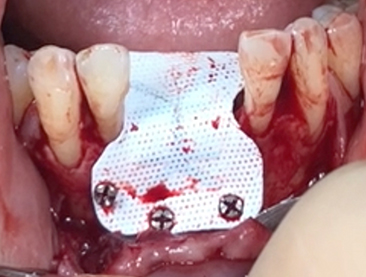

Another clinical case using non resorbable membrane and bone tac

• Another clinical case using  non resorbable membrane and bone tac 1

• Another clinical case using  non resorbable membrane and bone tac 2

• Another clinical case using  non resorbable membrane and bone tac 3

• Another clinical case using  non resorbable membrane and bone tac 4

• Another clinical case using  non resorbable membrane and bone tac 5

• Another clinical case using  non resorbable membrane and bone tac 6

• Another clinical case using  non resorbable membrane and bone tac 7

• Another clinical case using  non resorbable membrane and bone tac 8

• Another clinical case using  non resorbable membrane and bone tac 9

• Another clinical case using  non resorbable membrane and bone tac 10